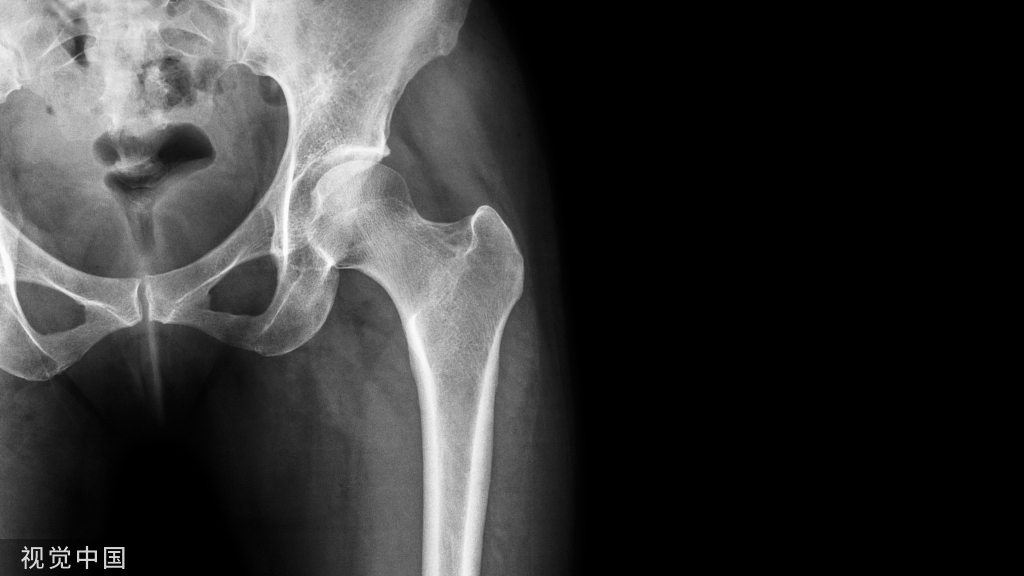

60岁以上非移位股骨颈骨折,内固定还是关节置换?

对移位股骨颈骨折,内固定通常导致较多的并发症。但对于非移位股骨颈骨折,采用内固定或关节置换的并发症风险尚无定论。 针对上述问题,有学者进行了相关研究,以对比对老龄(>60岁)非移位股骨颈骨折患者,采用内固定和关节置换在再手术率上是否存在差异?结果发表在2021.07 JOT期刊上。

与内固定相比,对于无移位和微小移位的老年股骨颈骨折患者,采用半髋关节置换治疗可降低70%再次手术的风险。[Conclusions:In elderly patients with nondisplaced and minimally displaced femoral neck fractures, treatment with hemiarthroplasty may reduce the relative risk of reoperation by 70% when compared with internal fixation.]